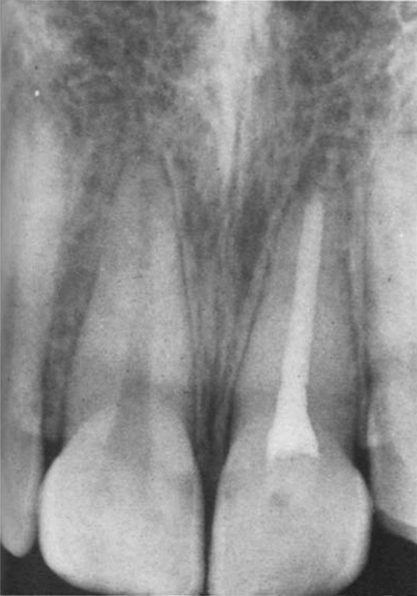

Через неделю цвет коронковой части приобрел исходный цвет. Вскоре после этого временная реставрация была заменена на силикатную. В 1970 году, спустя 3,5 года после отбеливания зуба, пациент вернулся с жалобами на подвижность пролеченного зуба. На слизистой оболочке с щечной стороны левого центрального резца в нескольких миллиметрах от края десны был выявлен свищевой ход. Рентгенограмма (рис. 3) показала, что, хотя эндодонтическое лечение было успешным, если судить по сохранности периодонтальной связки, симптомы пациента можно объяснить обширной наружной резорбцией в цервикальной области.

Рисунок 3. — Клинический случай 1 — Рентгенограмма через 34 года после лечения показала обширную наружную резорбцию как в мезиальном, так и в дистальном цервикальных отделах.